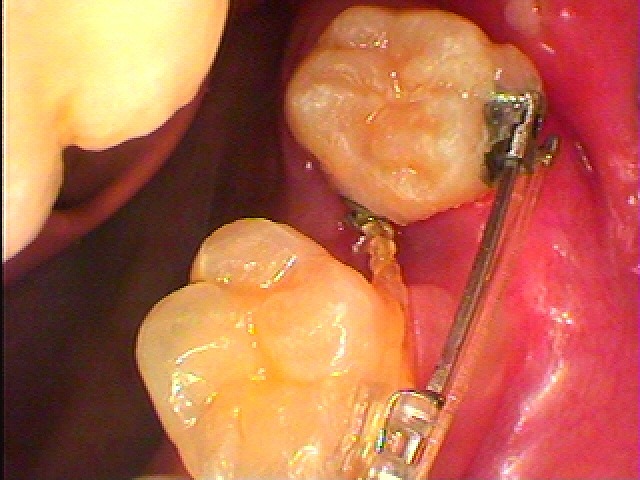

MTMにて8を7の位置に矯正移動 治療期間、半年以内の処置になります|お知らせ |広島市安佐南区の歯科医院 MTMにて8を7の位置に矯正移動 治療期間、半年以内の処置になります トップ お知らせ・ブログ お知らせ MTMにて8を7の位置に矯正移動 治療期間、半年以内の処置になります MTMにて8を7の位置に矯正移動 治療期間、半年以内の処置になります 抜歯をしたところになります 4,5,6番を固定源にして8の近心部低い位置にリンガルボタンにて 引っ張り上げます 6mmの隙間があります このように引っ張り上げています 傷も少しずつ治っていきます 抜歯後3日目になります 少しずつ寄ってきます さらに強くどちらからも引っ張り上げていきます 半年するとこのようにきれいにくっつきます Web診療予約 初めての方へ 選ばれ続ける理由 院内設備について 歯が痛いしみる一般歯科 歯がぐらぐらする歯周病 健康な歯を保ちたい予防歯科 子供の虫歯予防をしたい小児歯科 銀歯をセラミックに審美歯科 白い歯を目指しませんか?ホワイトニング 矯正専門医がいるので安心矯正歯科 抜けた歯を補いたいインプラント・入れ歯 医院案内 スタッフ紹介 メリィハウス歯科クリニックオフィシャルホームページ ラベンダー歯科クリニックオフィシャルホームページ お知らせ・ブログ ホーム 診療科目 一般歯科 歯周病治療 予防治療 小児歯科 審美治療 ホワイトニング 矯正歯科 入れ歯・インプラント マウスピース矯正 初めての方へ 院長・スタッフ 設備紹介 医院案内・アクセス メニューを閉じる